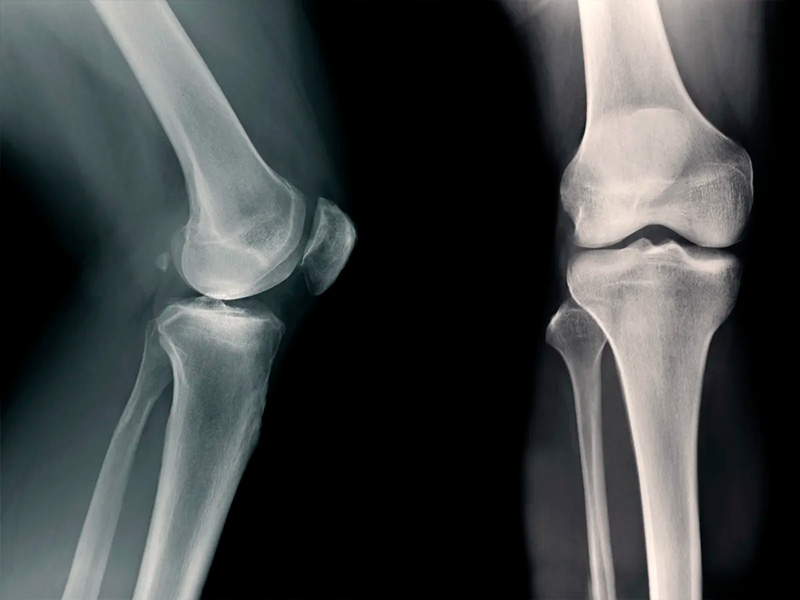

Остеоартроз долгое время воспринимался как неизбежное следствие возраста или износа суставов. Сегодня взгляд меняется: все больше внимания уделяется биохимическим процессам внутри хрящевой ткани и тому, как на них можно повлиять. Именно в этом контексте все чаще упоминается AOD 9604 – пептид, который изначально изучался совсем в другой области, но неожиданно показал интересные эффекты для суставов.

AOD-9604 - это фрагмент гормона роста, лишенный его системного действия. За счет этого он рассматривается как более безопасная молекула для точечного воздействия на ткани. В экспериментальных моделях исследователей заинтересовала его способность влиять на воспалительные реакции и метаболизм хряща. Речь идет не о восстановлении сустава «по щелчку», а о влиянии на среду, в которой развивается дегенерация. Именно поэтому AOD-9604 попал в фокус лабораторных и доклинических исследований.